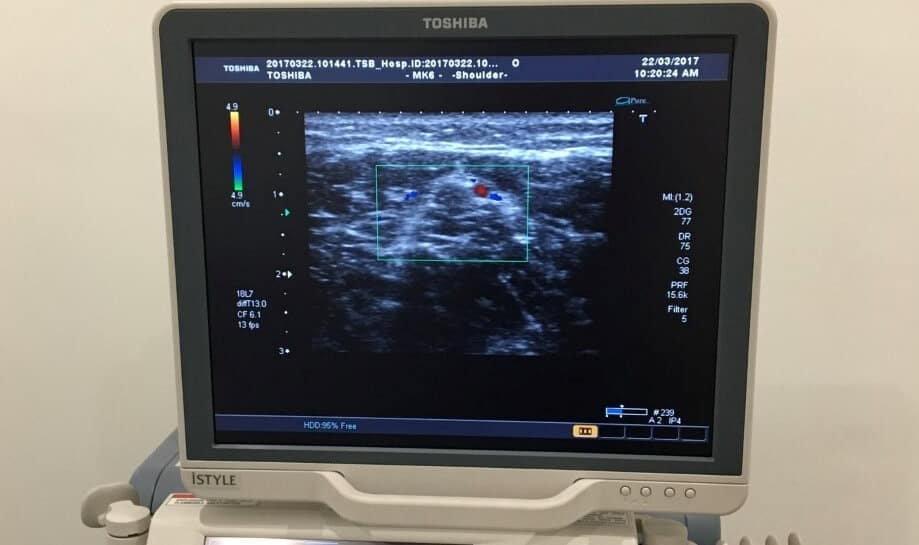

Ultrasound imaging provides information about the soft tissue structures of the foot. It is valuable for assisting to diagnose many soft tissue conditions.

Our podiatrists are able to perform onsite diagnostic ultrasound imaging to figure out what is causing your problem. Helping get to the cause of your problem.

Ultrasound Imaging at the Ankle and Foot Centre

Our lead clinician has done additional study and has experience diagnosing and reporting on ultrasonic images of the foot and ankle and using these to help guide treatment.

Ultrasound is beneficial in diagnosis of soft tissue injuries including Plantar Fasciitis, Achilles Tendinopathy, Forefoot pathology, Ankle sprain